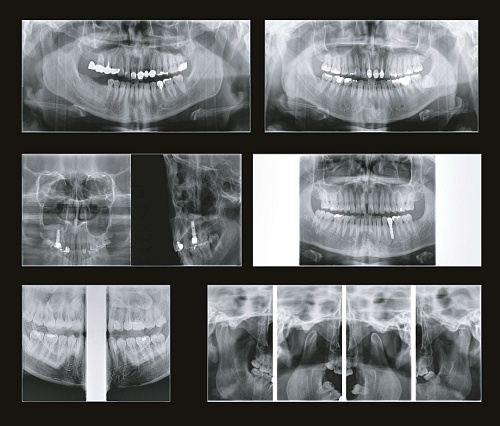

SMARF - алгоритм уменьшения вторичного улучшения от металлов дентального компьютерного 3D томографа.jpg